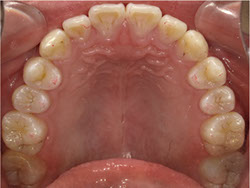

1期治療でスケルトンタイプの拡大装置で歯列拡大後、歯も抜かずにきれいになりました。

矯正前